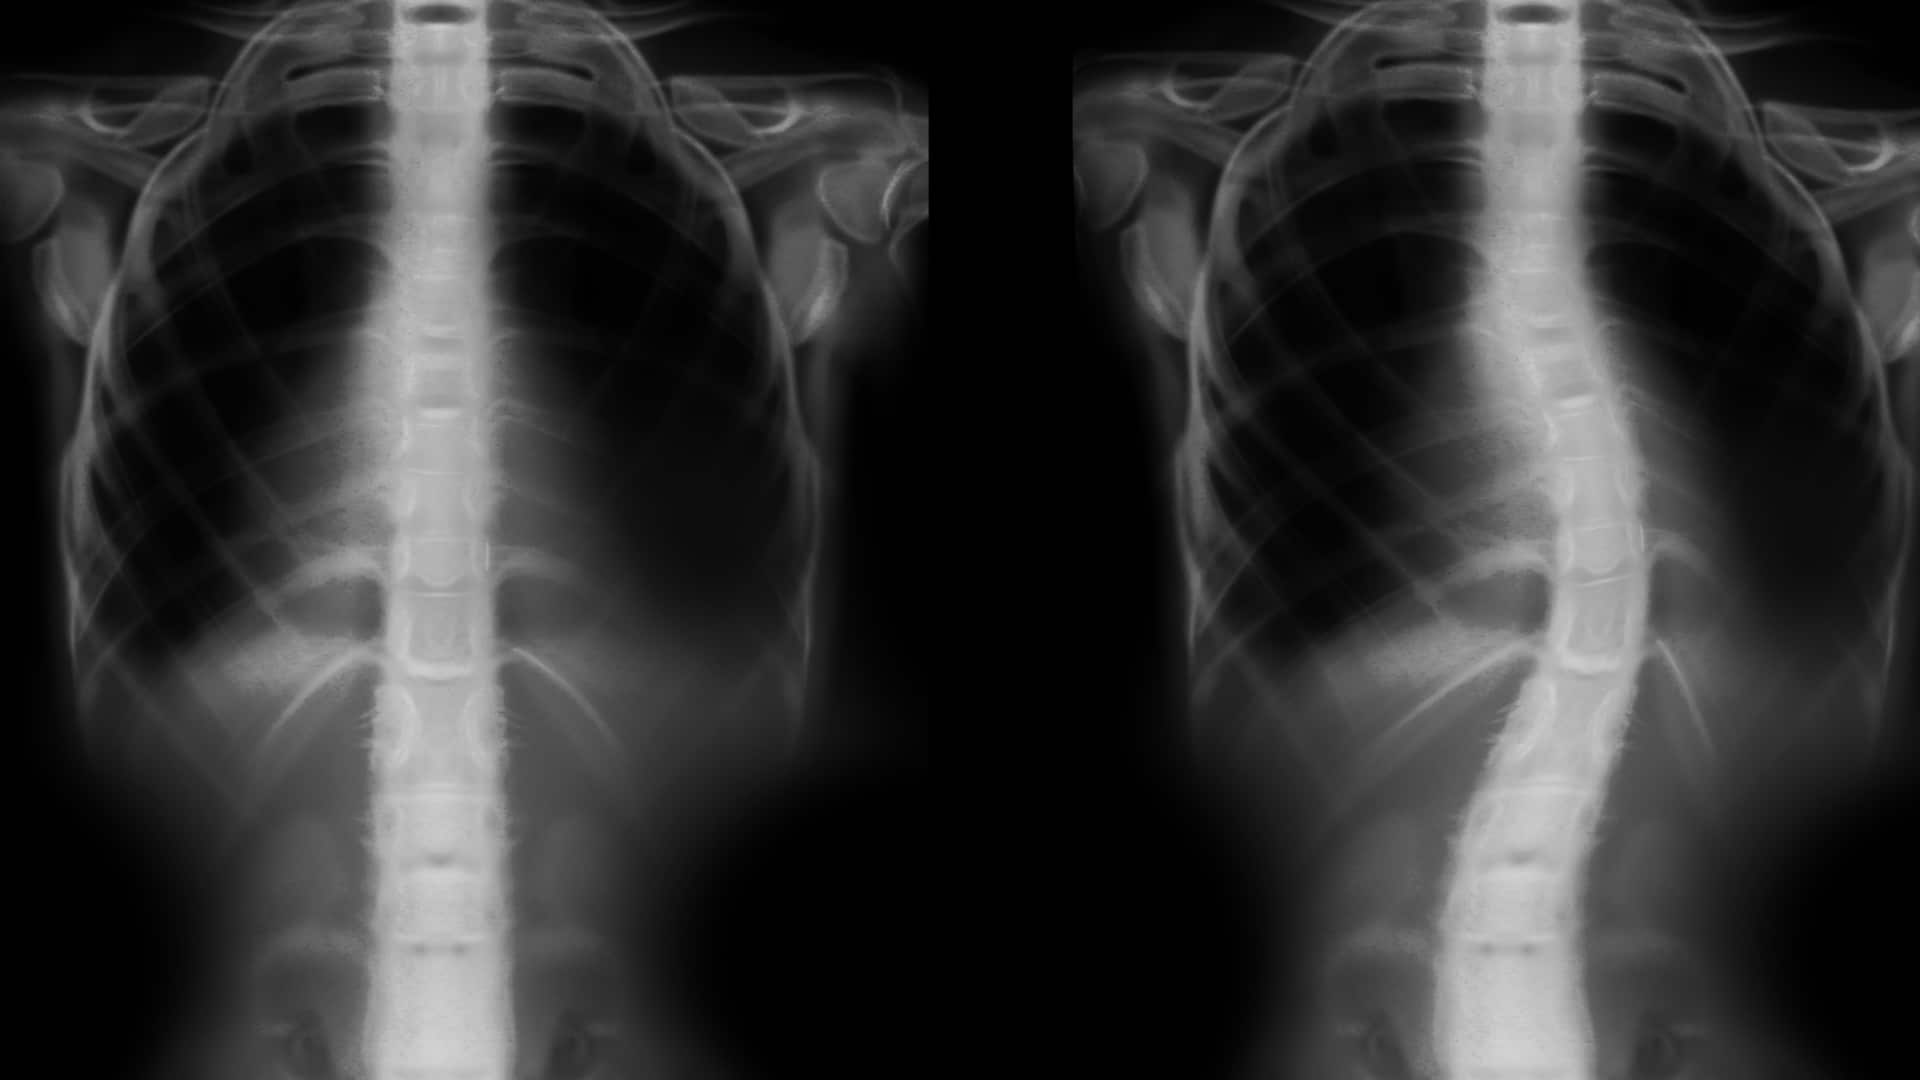

- угол искривления (по рентгену измеряют угол Кобба).